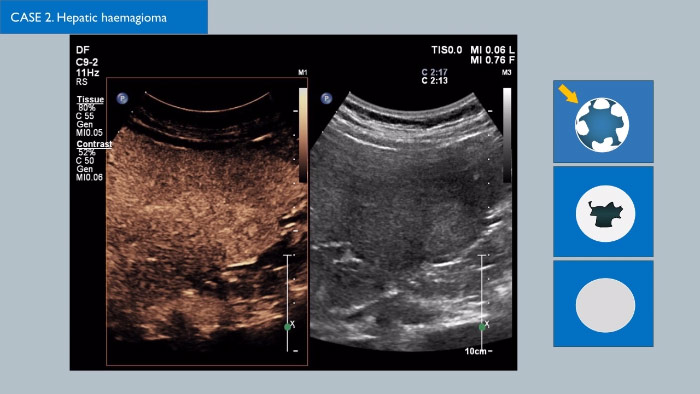

I mezzi di contrasto possono trasformare il ruolo dell'ecografia, permettendo ai medici di studiare i pattern di aumento del segnale di lesioni epatiche sospette in tempo reale e di giungere più velocemente all'elaborazione di diagnosi risolutive.

Con i sistemi ecografici Philips, l'ecografia con mezzo di contrasto si integra perfettamente nel flusso di lavoro standard riuscendo a fornire dettagli eccellenti durante la scansione delle fasi arteriosa, portale e tardiva. Grazie inoltre ad avanzate tecnologie come MaxVue, il trasduttore C9-2 PureWave, la fusione di immagini, la quantificazione integrata tramite le Q-App Philips e la soluzione specifica per il fegato, la massima affidabilità è ormai la norma anche negli esami tecnicamente più difficili. Innovative soluzioni come la tecnologia 3D/4D xMatrix trasformano la valutazione delle lesioni epatiche e forniscono un modo rapido ed efficace per visualizzare i vasi che le alimentano e la risposta alla terapia. Si stanno preparando molti sviluppi interessanti nel campo dell'ecografia con mezzo di contrasto, fate clic sul collegamento per contattare l'ufficio vendite Philips di zona.